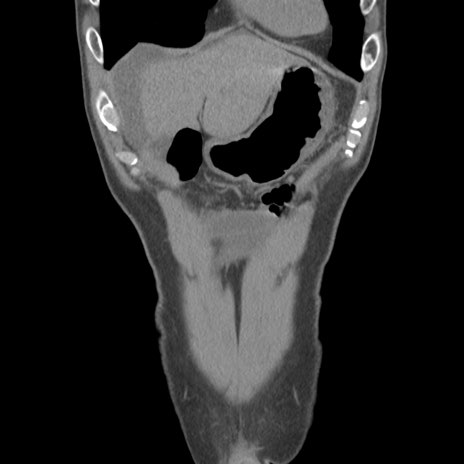

症例56 CT(冠状断像)

脂肪ウインドウ